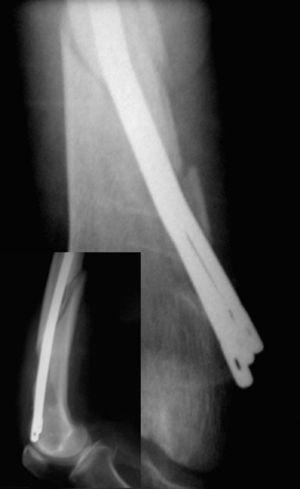

Resultado radiológicoSegún los parámetros de Harper y Walsh 8 , aparecieron 279 casos (75%) de buenas reducciones, 53 casos (14%) en varo y 40 casos (11%) de reducciones en valgo. La colocación de los clavos fue correcta en la proyección AP en 216 pacientes (58%) y en 238 (64%) en la proyección axial, consiguiendo el relleno del canal medular en 234 casos (63%). El tiempo medio de consolidación fue de 11,4 semanas (fig. 2).

Figura 2. Buena consolidación a las 12 semanas de una fractura per subtrocantérea femoral; en la imagen pequeña (abajo a la derecha) se muestra el buen relleno del canal medular.